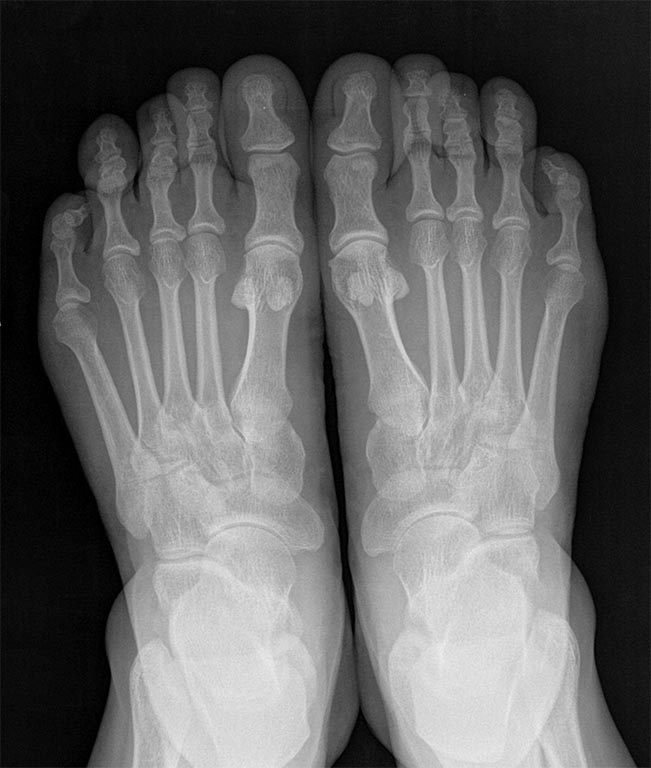

Уважаемый господин Бережной. Но вы же понимаете что это не диагноз. Посмотрите на нечто подобное, правда чуть более выраженное.

Конечно то, что я написал - не диагноз. Я и сказал, что в МКБ такого не найдешь. Но и болезни никакой нет. Случай, который Вы продемонстрировали, интересный. Было бы еще интереснее увидеть эту стопу до операции. Чтобы понять, насколько толще стал оперированный палец в финале. А вот сходства Вашего случая с обсуждаемым я не увидел. В предложенном на форум случае третий палец явно тоньше соседних и пятого. Скорее можно говорить о гипоплазии третьего пальца. Хотя, какая разница? Жалоба больной понятна. Как устранить слегка избыточную длину 4-го пальца тоже, вроде, понятно. Вы же не советуете сделать такую же операцию, как в Вашем примере? Если же говорить о похожем случае, то и я предлагаю посмотреть на нечто подобное.

Пациентка жаловалась на избыточную длину третьих пальцев. И шишки в проекции головок М5 (болезнь портных). Вроде все выровнял. Сейчас, через 3 года после первой операции, она едет делать уже третьи операции на обеих стопах. Теперь хочет укоротить все пальцы. Вот о такого рода пациентках я и предупреждал автора поста

Финал. Диагноз пациентки - истинный врожденный гигантизм 2 пальца стопы. На сегодняшний день описаны 3 формы - с преимущественным увеличением мягких тканей, с равномерным увеличением тканей, с преимущественным увеличением мышечных тканей.